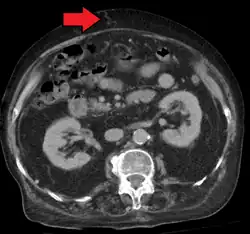

In addition, a widened (dilated) portal vein as seen on a CT scan or MRI may raise the suspicion about portal hypertension. A cutoff value of 13 mm is widely used in this regard, but the diameter is often larger than this is in normal individuals as well.[9]

Ultrasonography (US) is the first-line imaging technique for the diagnosis and follow-up of portal hypertension because it is non-invasive, low-cost and can be performed on-site.[17]

A dilated portal vein (diameter of greater than 13 or 15 mm) is a sign of portal hypertension, with a sensitivity estimated at 12.5% or 40%.[18] On Doppler ultrasonography, a slow velocity of <16 cm/s in addition to dilatation in the main portal vein are diagnostic of portal hypertension.[19] Other signs of portal hypertension on ultrasound include a portal flow mean velocity of less than 12 cm/s, porto–systemic collateral veins (patent paraumbilical vein, spleno–renal collaterals and dilated left and short gastric veins), splenomegaly and signs of cirrhosis (including nodularity of the liver surface).[17]

The hepatic venous pressure gradient (HVPG) measurement has been accepted as the gold standard for assessing the severity of portal hypertension. Portal hypertension is defined as HVPG greater than or equal to 5 mmHg and is considered to be clinically significant when HVPG exceeds 10 to 12 mmHg.[20]